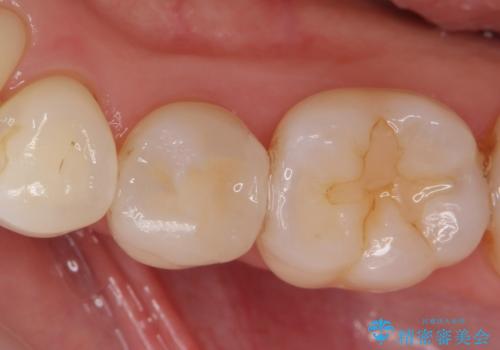

コンタクトカリエス

- レントゲンで虫歯(コンタクトカリエス)が見られたので拡大鏡で虫歯を取り除いた後、e-maxインレー(セラミックインレー)で治療を行いました。